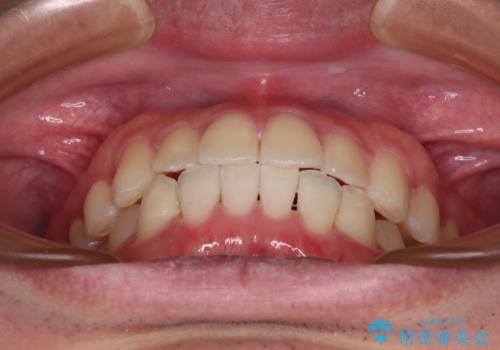

【モニター】前歯のクロスバイトと隙間を改善 インビザラインによる矯正治療

- 前歯のクロスバイトを気にして来院された患者様です。

骨格的には問題がなかったため、インビザラインを用いて咬み合わせを改善していくこととしました。

インビザライン特有の、奥歯の咬み合わせの問題もなく、しっかりと歯列を改善することができました。

舌側転位している上顎側切歯(内側に引っ込んでいる真ん中から2番目の歯)は、インビザラインが最も移動を苦手とする歯であり、これ以上の改善を望まれる場合にはワイヤー矯正、あるいはワイヤー矯正の併用をお勧めいたします。